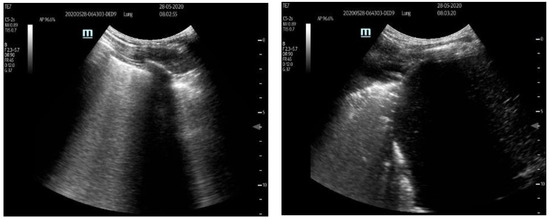

2. Materials and Methods

2.2. Methods